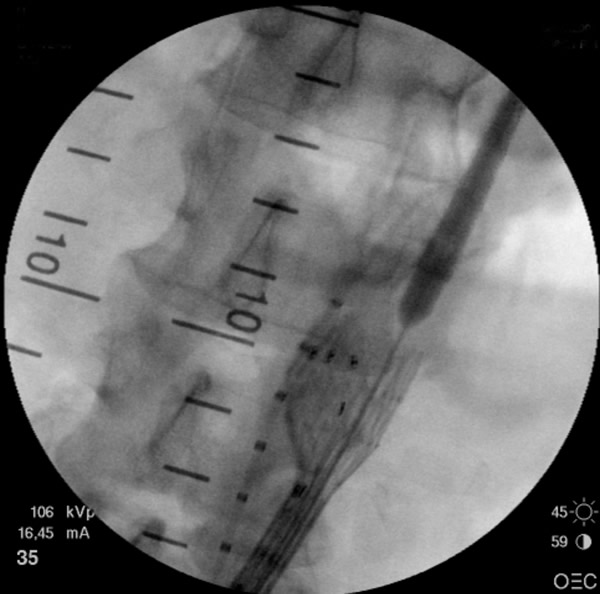

- The main trunk is flushed with heparinized solution, advanced into the proximal neck, positioned just inferior to the lowest renal artery, and oriented so that the contralateral limb gate can be easily accessed. The orientation of the contralateral gate is performed using the manufacturer’s radiopaque markers at the crown of the trunk and/or the stent graft bifurcation under fluoroscopic guidance. A repeat angiogram is commonly performed to reconfirm the positioning of the device within the aorta. Subsequently, the main trunk is deployed (Figures 2, 3), opening the contralateral limb gate.